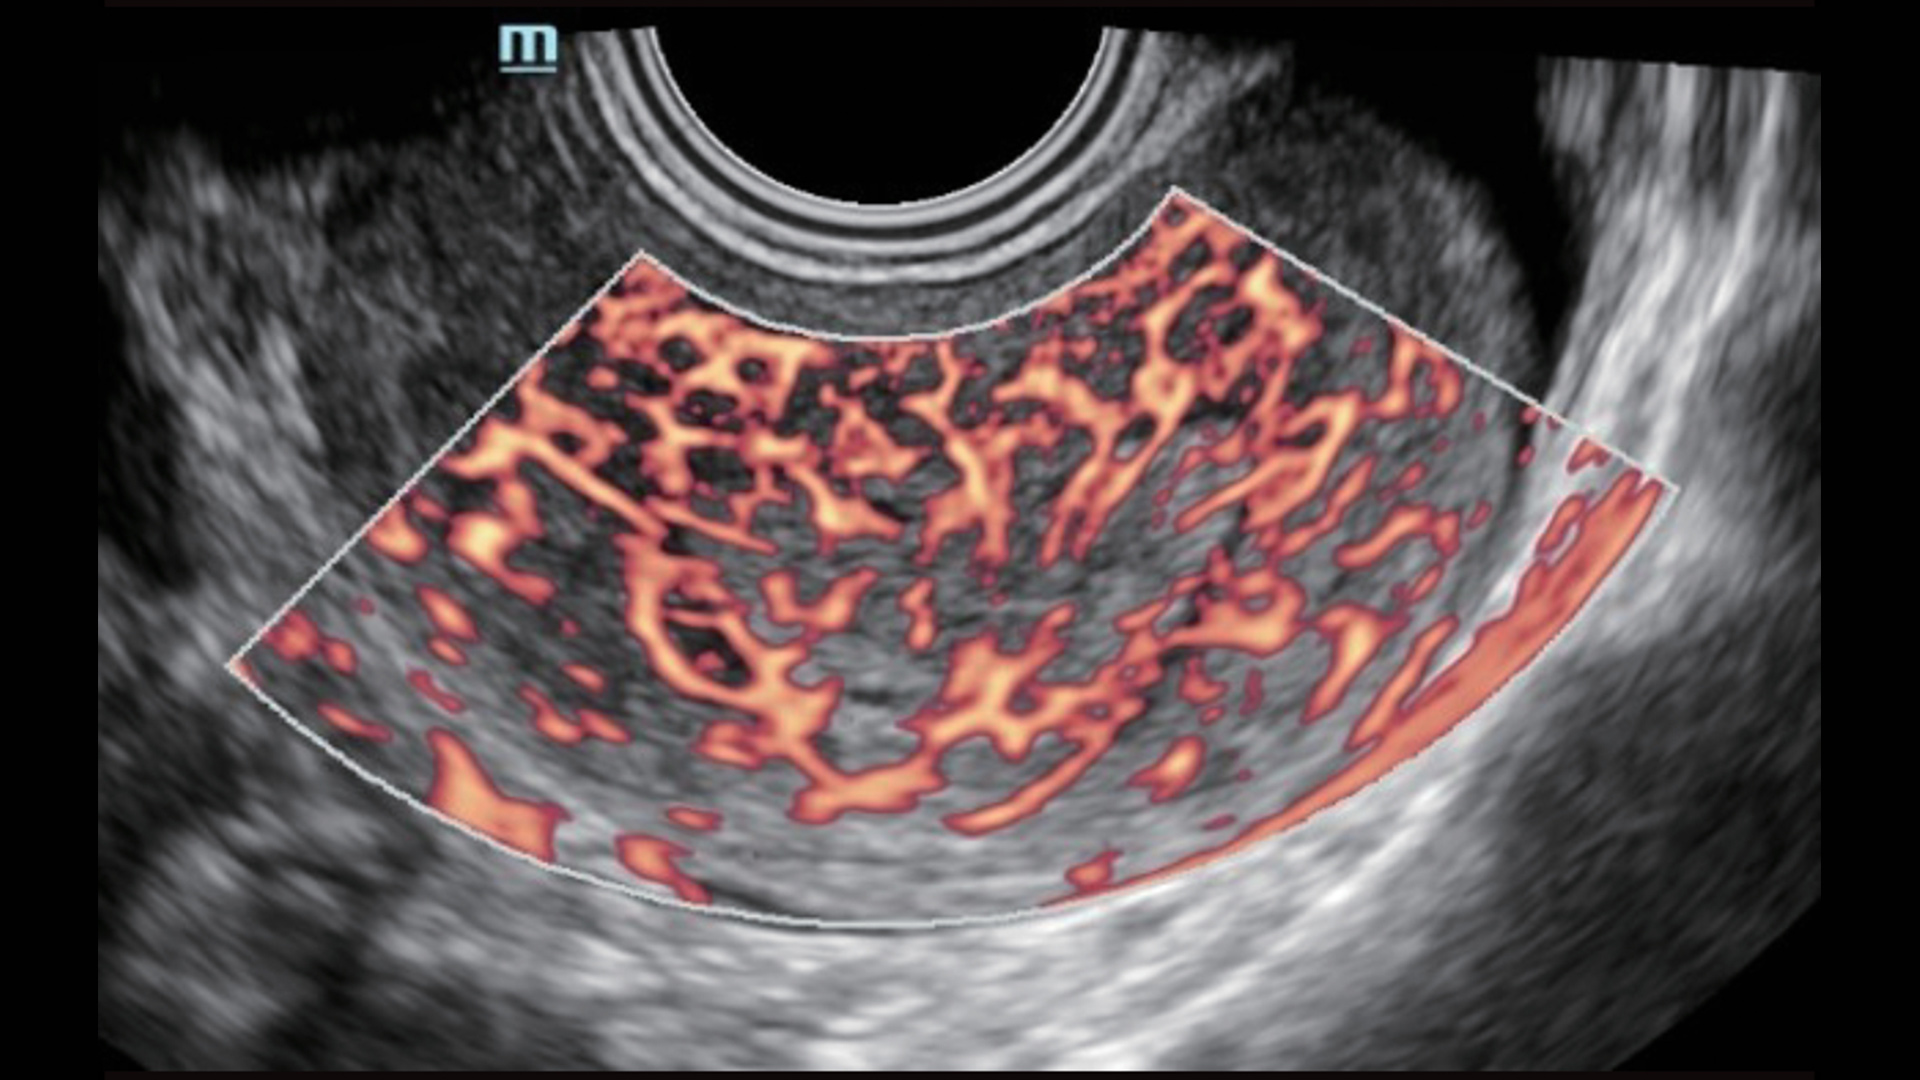

UMA (Ultra-Micro Angiography)

The innovative technology breaks the bottlenecks of traditional Doppler imaging. With ultra-high spatial resolution and flow sensitivity, it allows detecting super-subtle and super-slow flow perfusions, thereby extending the clinical application of qualitative and quantitative ultrasound evaluation in fetal brain, kidney, placenta, endometrium, ovary, etc.

UMA - uterine and endometrial flow